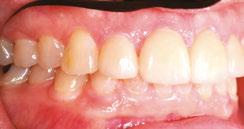

Figures 6 through 9 demonstrate a patient successfully treated with NiTime Aligners following the patient’s rejection of other systems. Figures 6 and 8 display pre- and posttreatment photos of a patient that presented with a Class II malocclusion and normal OB/OJ. This patient has teeth Nos. 7 and 10 missing congenitally. Note that the patient was treated as a child and has a canine substitution due to the missing lateral incisors. Recession was noted on tooth Nos. 2,3, 4, 5, 9, 11, 13, 14, 22, 24, 26, and 27. The patient tried labial and lingual brackets unsuccessfully, as well as a leading clear aligner to correct her malocclusion as an adult. In all three treatments, the patient could not tolerate the mechanics due to increased discomfort and was unable to complete therapy.

It is important to note that there was no refinement required for this case, and the patient finished in 26 weeks with 26 trays. Although the patient presented with significant recession, it did not worsen with treatment. As demonstrated in Figure 9, teeth aligned as planned by the OrthoFX treatment plan shown in Figure 7. Overlays of the actual results with the original treatment plan indicate a high level of predictive accuracy. Not only was a satisfactory result produced from the patient wearing the aligners, but the accuracy is quite high for the NiTime material despite the patient wearing it significantly less than the traditional 22 hours per day.

Figure 6: Class II malocclusion pretreatment

Figure 8: Class II malocclusion posttreatment. Left column pretreatment. Right column posttreatment 22 stages